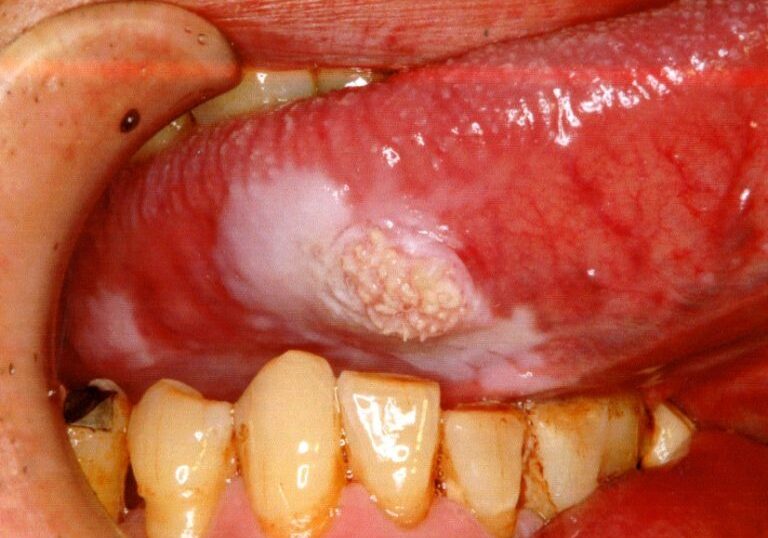

舌の右側に薄い白色を呈した領域がみられます。 その中央には厚みがあって,疣のようなものがみえます。このような場合でも,“白板症(はくばんしょう)”と診断されるのでとりあえず経過観察とされることもあります。以前のブログにて経過観察とせず切除した結果,転移のリスクが高い癌であることが判明した例を御紹介しました。この方も早く取って正解だったケースで,癌でした。もし,“白板症”が生じたら長く放置しないで大学病院などの口腔外科への受診をお勧めします。